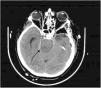

This is the case of a 75-year-old man treated with scheduled surgical clipping of a giant aneurysm at left internal carotid artery level. After surgery, a cranial CT scan performed revealed the presence of an image consistent with acute ischemia in the left frontal region. Twenty-four hours later, right side mydriasis was reported. This new finding prompted a new cranial CT scan that revealed the progression of ischemic phenomena with damage to the left middle and posterior cerebral artery territories (Fig. 1) with signs of intracranial hypertension and compression at brainstem level against the contralateral tentorium (Fig. 2), which would explain the midriasis of the right side. This is know as the Kernohan-Woltman notch phenomenon. Despite medical treatment, the option of decompressive craniectomy was ruled out, and the patient progressed to brain death.